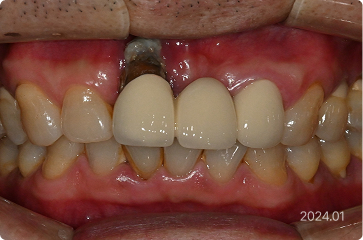

59세, 남 ㅣ 앞니 임플란트

“앞니 뿌리가 다 보여서 보기에 너무 안 좋아요.”

치료 전

원데이 임플란트

치료 후

• 앞니 뼈 흡수 및 뿌리 과다 노출

• 원데이 임플란트로 잇몸 및 치아 형태 복구

• 발치,식립 > 최종 보철 약 2개월 내 완성